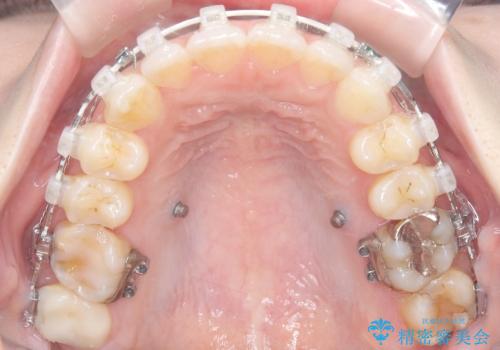

- 治療計画

今回のワイヤー矯正治療では、抜歯せずに歯を並べるスペースを作るため、特殊な小さなインプラントであるアンカースクリュー(TAD)を一時的に使用しました。このアンカースクリューを固定源として、奥歯(臼歯部)全体を後方へ遠心移動させました。従来の矯正では難しかったこの奥歯の移動を確実に行うことで、前歯の八重歯を適切な位置に並べるスペースを確保。治療の結果、抜歯することなく右上の八重歯と叢生が解消され、機能的にも審美的にも整った美しい歯並びを獲得していただけました。